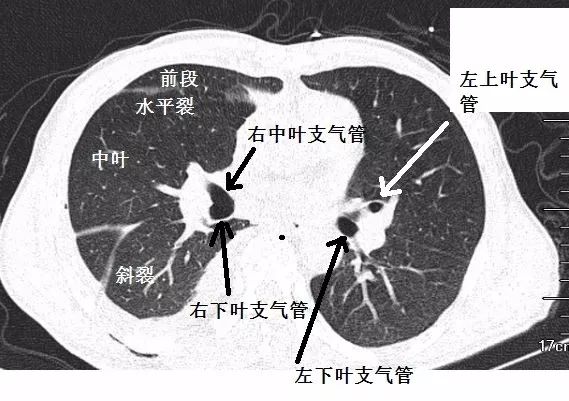

胸部CT入门之一,便是肺部分段,分段的基础,便是支气管解剖。

多说无益,看图(从上往下的解剖图):

尖段支气管位置最高!

前面的叫前段支气管,后面的叫后段支气管。

双侧下叶支气管,指向背部的第一个分支,就是背段支气管。

中叶,靠近心脏的是内侧段支气管,另外一支则是外侧段支气管。

内、前、外、后基底段支气管,都是依据方位来分的,靠近心脏的是内,靠近脊柱的是后。

斜裂非常关键,是肺段分界的铁证!